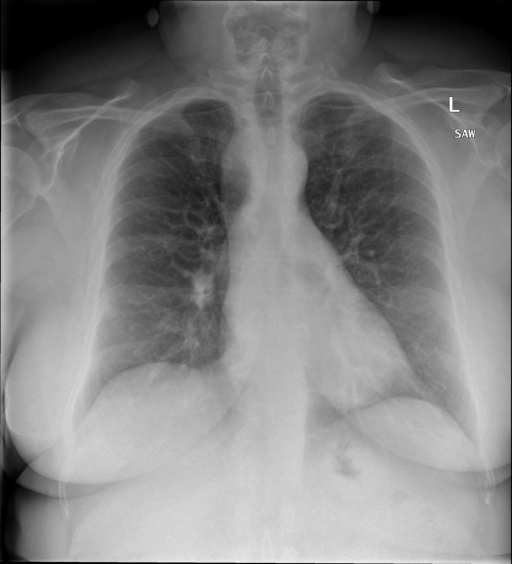

- (1)准备[诊疗报告(中文)](./data/Xray/openi-zh.json)和[X光影像](https://pan.baidu.com/s/13GBsDMKf6xBZBSHpoWH_EA?pwd=k9sh)在`data/Xray`文件夹下; - (2)开始训练: ```bash # 设置CUDA变量,主要是为了解决有时候直接训练而出现无法正确加载到显卡问题 export CUDA_VISIBLE_DEVICES=0,1,2,3 # 开始训练 bash finetune_XrayGLM.sh ``` 这里的复现过程非常简单,主要是很多过程我们都为大家准备好了,大家可以随时复现一个自己的`XrayGLM`。 ### 4.模型训练(通用) - [【官方视频教程】XrayGLM微调实践](https://www.bilibili.com/video/BV1Yh4y147gx/) - [复旦大学《大语言模型理论与实践》](https://intro-llm.github.io/) ## 效果展示 *以下效果来自于**低质量**的数据训练和权重 影像诊断: |X光影像|诊疗报告(医生)|XrayGLM| |:-|:-|:-| |![](./data/Xray/2_1.png)|根据X射线图像,心脏大小正常,肺部看起来很清晰。已经排除了肺炎、积液、水肿、气胸、腺病、结节或肿块的存在。该发现表明一切正常。换句话说,总体印象是胸部正常。|X光片显示,心脏大小正常。肺部没有气胸或胸腔积液的证据。骨骼结构看起来没有任何异常。总的来说,X光片表明没有发现急性心肺疾病的迹象。| |![](./data/Xray/2882_1.png)|X光图片显示没有扭曲的区域、可疑的骨质不透明度或胸腺积液。心脏大小轻微增大,但非常稳定。此外,没有气胸的证据,肺野也正常。总体来说,X光片显示没有急性心脏异常,但要注意轻微的心脏扩大。|X光片显示,心脏大小正常。肺部和纵隔轮廓清晰,没有气胸或胸腔积液的证据。骨骼结构完整,没有任何急性异常。| |![](./data/Xray/2577_1.png)|心影形态在正常范围内。没有急性骨质异常。有可能出现没有明显的吸水或肺实质状况的线索。没有大面积积液或气胸。有可能怀疑其有误吸或肺实质问题。为了确诊和治疗,可能需要进行适当的影像学随访。|心脏大小正常,肺部和纵隔轮廓清晰。没有急性异常或活动受限的证据。没有任何明显的气胸、胸腔积液或肺不张的迹象。此外,也没有发现任何局灶性骨质异常或其他急性疾病。| 多轮对话: |X光影像|诊疗报告(医生)| |:-|:-| |![](./data/Xray/861_1.png)|右侧主动脉突出观察到。心脏大小正常。胸部未发现明显的肺气肿、胸膜积液或可疑的肺部病变。报告指出已知右侧主动脉情况正常。| ```bash >> X光影像路径:./data/Xray/861_1.png >> 用户:这是一张什么图? >> XrayGLM:这张图片显示的是一张肺部检查的X光片。 >> 用户:请描述这张胸部X光片的诊断结果 >> XrayGLM:心脏大小正常,肺部清晰。没有急性心肺疾病的证据。 >> 用户:是否存在肺气肿? >> XrayGLM:没有肺气肿。心脏大小正常,肺部清晰。没有发现急性心肺疾病的证据。 >> 用户:平时饮食该注意什么? >> XrayGLM:饮食应该健康,均衡。建议增加蛋白质的摄入量,因为蛋白质有助于维持肌肉和骨骼的健康。多食用蔬菜、水果、全谷物以及健康的脂肪来源如橄榄油、鱼类等可以帮助获得足够的维生素和矿物质。此外,避免过度饮酒或吸烟,这些习惯可能会对心脏健康产生负面影响。 ``` ## 未来展望 1. 模型的能力更多来源于数据的支持,`OpenI-zh`作为微调数据集,其数据量足以支持研究,在更广泛的任务和性能表现上,我们认为**在大规模数据集上预训练并在高质量少量数据集上微调是一种可行的方案**; 2. 普遍意义的理解上,视觉多模态模型=视觉模型+语言模型。除了需要关注视觉模型信息与语言模型输出的搭配外,还需要**额外关注到语言模型的加强,在人机的对话中,尤其是医疗语言模型的问答上,除了专业的医疗问题回答,带有人文情怀的有温度的回答更应该是我们追寻的目标**。 3. **高精度的模型永远打不过大参数的模型**,如果在6B模型和13B模型上选择微调,请在资源充足情况下选择13B的大参数模型; ## 项目致谢 1. [VisualGLM-6B](https://github.com/THUDM/VisualGLM-6B)为我们提供了基础的代码参考和实现; 2. [MiniGPT-4](https://github.com/Vision-CAIR/MiniGPT-4)为我们这个项目提供了研发思路; 3. ChatGPT生成了高质量的中文版X光检查报告以支持XrayGLM训练; 4. [gpt_academic](https://github.com/binary-husky/gpt_academic)为文档翻译提供了多线程加速; 5. [MedCLIP](https://github.com/RyanWangZf/MedCLIP) 、[BLIP2](https://huggingface.co/docs/transformers/main/model_doc/blip-2) 、[XrayGPT](https://github.com/mbzuai-oryx/XrayGPT) 等工作也有重大的参考意义; ![](./assets/images/mpu.png) 这项工作由[澳门理工大学应用科学学院](https://www.mpu.edu.mo/esca/zh/index.php)硕士生[王荣胜](https://github.com/WangRongsheng) 、[段耀菲](https://github.com/IsBaSO4) 、[李俊蓉](https://github.com/lijunrong0815)完成,指导老师为檀韬副教授、[彭祥佑](http://www.patrickpang.net/)老师。 *特别鸣谢:[USTC-PhD Yongle Luo](https://github.com/kaixindelele) 提供了有3000美金的OpenAI账号,帮助我们完成大量的X光报告翻译工作 ## 免责声明 本项目相关资源仅供学术研究之用,严禁用于商业用途。使用涉及第三方代码的部分时,请严格遵循相应的开源协议。模型生成的内容受模型计算、随机性和量化精度损失等因素影响,本项目无法对其准确性作出保证。即使本项目模型输出符合医学事实,也不能被用作实际医学诊断的依据。对于模型输出的任何内容,本项目不承担任何法律责任,亦不对因使用相关资源和输出结果而可能产生的任何损失承担责任。 ## 项目引用 如果你使用了本项目的模型,数据或者代码,请声明引用: ```bash @misc{wang2023XrayGLM, title={XrayGLM: The first Chinese Medical Multimodal Model that Chest Radiographs Summarization}, author={Rongsheng Wang, Yaofei Duan, Junrong Li, Patrick Pang and Tao Tan}, year={2023}, publisher = {GitHub}, journal = {GitHub repository}, howpublished = {\url{https://github.com/WangRongsheng/XrayGLM}}, } ``` 我们的工作被[Evaluating Large Language Models for Radiology Natural Language Processing](https://arxiv.org/abs/2307.13693)引用,希望大家去关注一下相关的工作! ## 使用许可 此存储库遵循[CC BY-NC-SA](https://creativecommons.org/licenses/by-nc-sa/4.0/) ,请参阅许可条款。